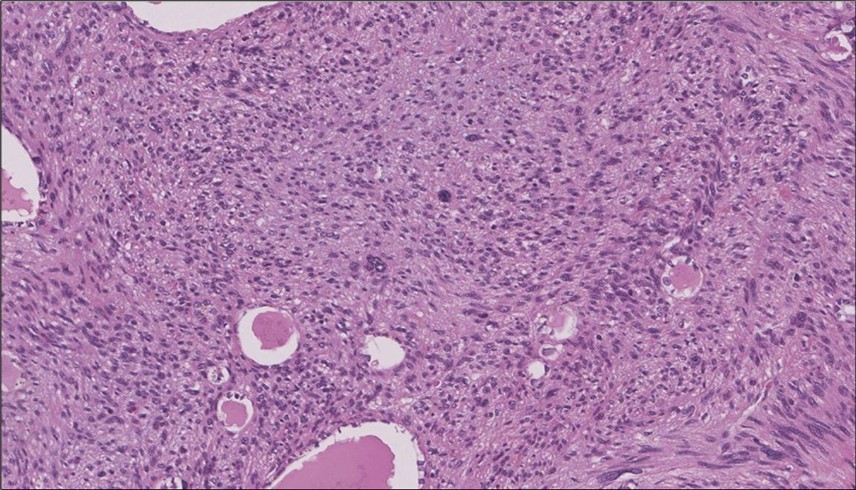

When diagnosing thyroid swelling, imaging studies have been helpful in differentiating malignant from benign tumors with US being used as an initial evaluation tool when assessing thyroid nodules. Tumors are categorized based on composition, echogenicity, shape, margin and echogenic foci into added scores determined by the TI-RADS system, which determines the need for FNA 13. Other imaging modalities include MRI and CT. However; radiological assessment does not distinguish between the types of thyroid cancer, and therefore FNA and biopsy are of crucial importance 3, 6. On a pathologic sample, LMS appears as spindled eosinophilic cells with elongated blunt-ended or cigar-like nuclei arranged in fascicles 2, 7 (Figure 1, Figure 2, Figure 3). Despite the unique microscopic morphology, LMS cannot be distinguished from other spindle cell tumors such as spindle cell variant of medullary thyroid cancer, anaplastic thyroid

Figure 3.Left thyroid The malignant looking cells are showing diffuse atypia, mitosis and hyper-chromatic nuclei, some remaining follicles could be noted as well (H&E, ×400).

cancer, or other metastatic tumors without further testing with genetic or molecular studies 3, 7. Immunohistochemical testing plays a vital role in differentiating LMS from such similar tumors as it stains positive for vimentin and smooth muscle actin (SMA), and is variably positive for HHF35, desmin (50%-100%), and H-caldesmon 3, 6. Moreover, there were no reported cases where thyroid LMS stained positive for thyroglobulin, cytokeratin, calcitonin, chromogranin, or protein S100 3. Our patient’s left thyroid biopsy showed the characteristic microscopic features and was positive for SMA, desmin, caldesmon, P63 with patchy EMA (Figure 1, Figure 2, Figure 3, Figure 4) as well as her liver biopsy (Figure 5, Figure 6, Figure 7); whereas her right thyroid showed clear papillary thyroid cancer cell features (Figure 8, Figure 9).